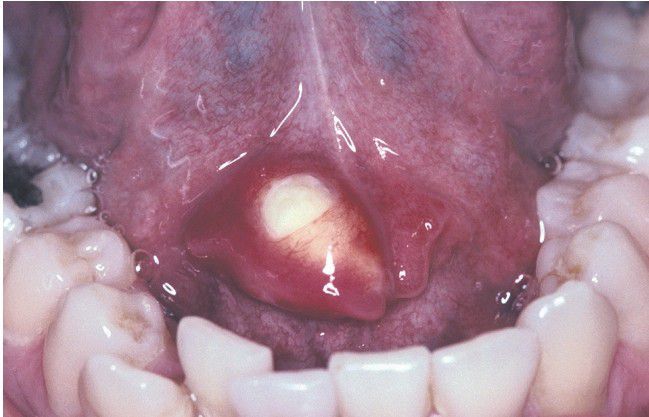

Sialolithiasis

. Hard mass at the orifice of Wharton duct.